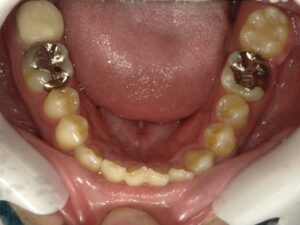

初診時の口の中の写真です。

今回の場合は、親知らずが隣に存在し虫歯もない状況です。

内側から見た状態です。

動きに合わせてゴムの力を変えて、歯を引っ張っていきます。